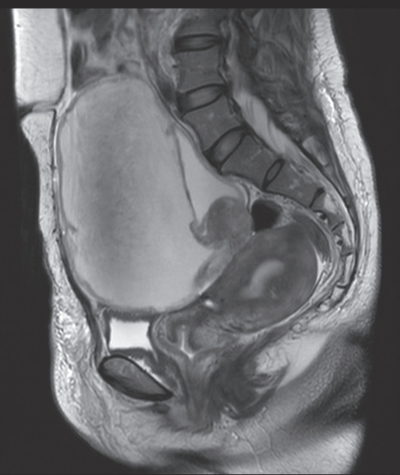

腫瘍マーカーは、CA19-9 87 U/mL(基準 37以下)、CA125 235 U/mL(基準 35以下)。骨盤部単純MRIのT2強調矢状断像を別に示す。胸腹部CTで転移や播種を認めない。